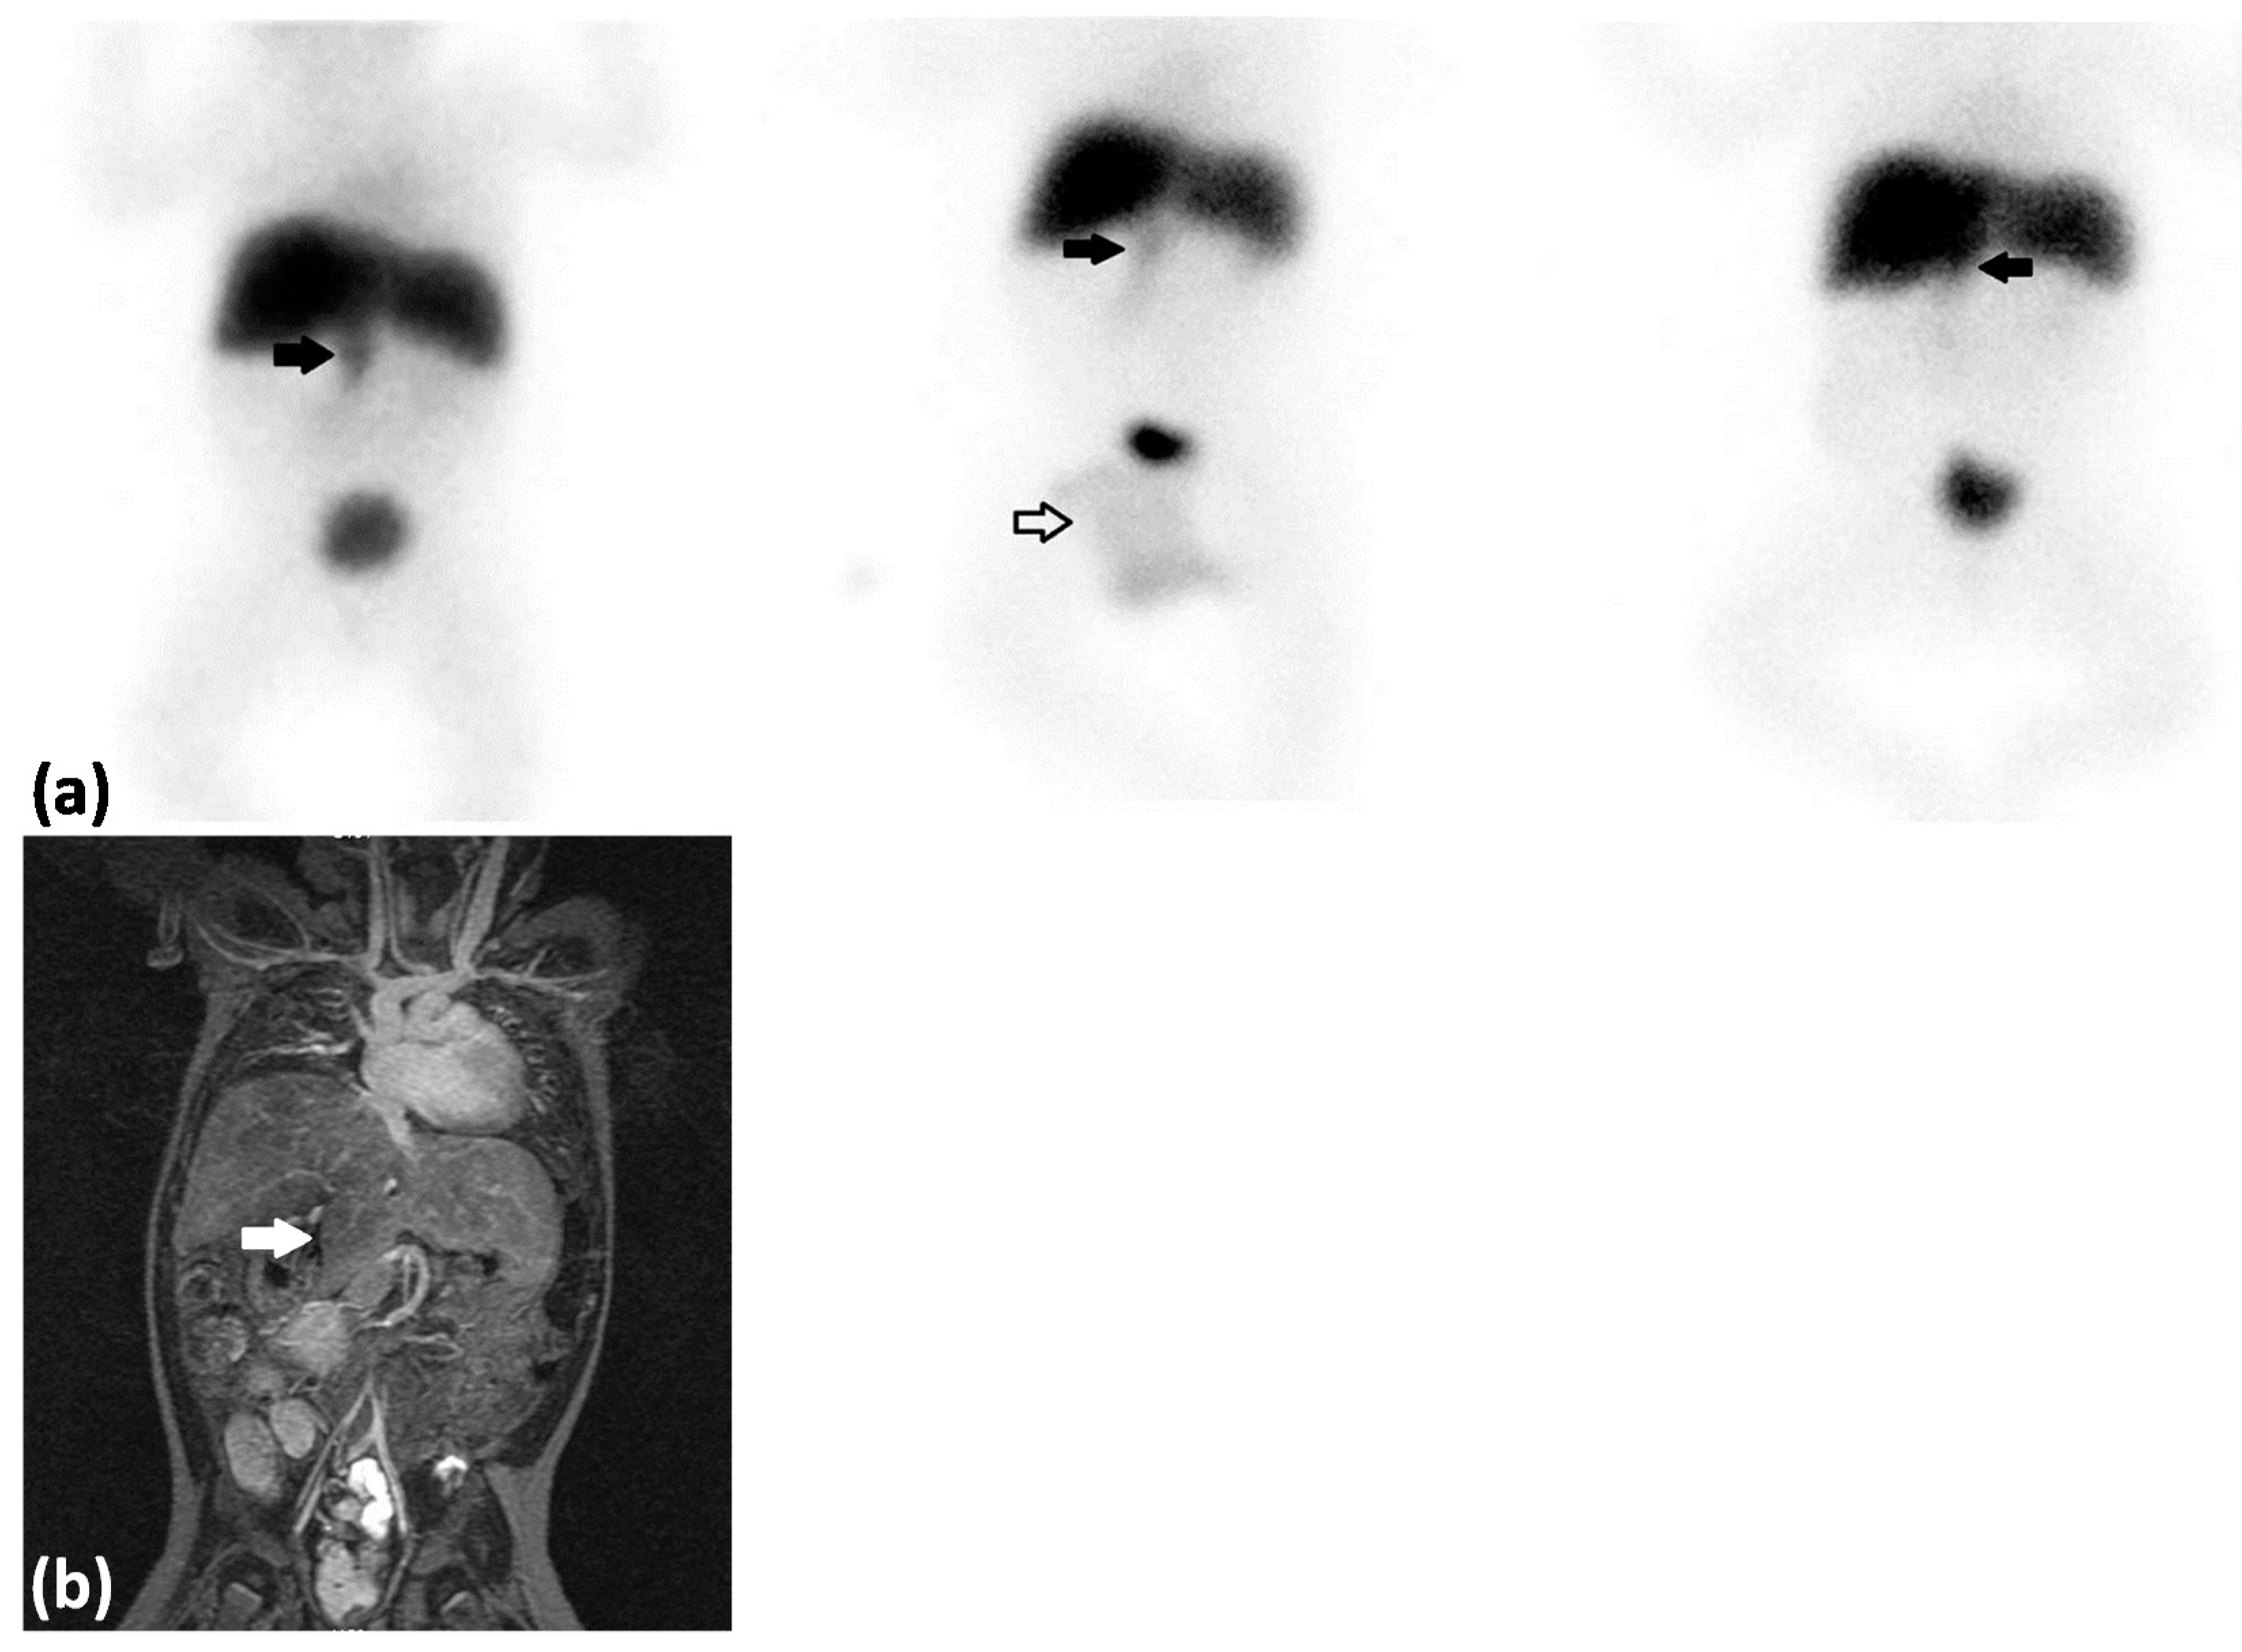

Figure 1.

(a) 99mTc-Mebrofenin hepatobiliary scintigraphy anterior view—left: summarized dynamic images 52–56 min after tracer injection; middle: static image 2 h after tracer injection; right: static image 5 h after tracer injection. A 21 day old girl with known situs inversus of the stomach diagnosed in relation to an operation for malrotation and duodenal atresia who presented with jaundice. Laboratory work-up showed conjugated hyperbilirubinemia (total bilirubin, 239 µmol/L (normal range 4–17 µmol/L), conjugated bilirubin, 191 µmol/L (normal range <4 µmol/L)), elevated alanine aminotransferase (ALT, 57 U/L (normal range 10–45 U/L)), elevated aspartate aminotransferase (AST, 94 U/L (normal range 15–65 U/L)), normal alkaline phosphatase (ALP, 415 U/L (normal range 55–425 U/L)), and elevated gamma-glutamyl transpeptidase (GGTP, 1021 U/L (normal range 10–130 U/L)). Biliary atresia (BA) was suspected and the patient was referred for a 99mTechnetium-trimethylbromo-iminodiacetic acid hepatobiliary scintigraphy (99mTc-Mebrofenin hepatobiliary scintigraphy) which showed rapid extraction of tracer by the liver with no excretion to the small bowl but with suspicion of visualization of the gallbladder (thick black arrows). Tracer was physiologically excreted with the urine and localized in a diaper (white arrow). Rapid tracer extraction by the liver is indicative of normal functioning hepatocytes which can be expected in BA and in part rule out neonatal hepatitis which is a differential diagnosis to BA in infants with conjugated hyperbilirubinemia. No excretion of tracer to the small bowl indicates BA but visualization of the gallbladder is not common in BA since the common bile duct is affected in the majority of cases []. Because of the known altered anatomy and the somewhat unexpected result of the 99mTc-Mebrofenin hepatobiliary scintigraphy it was decided to perform a laparotomy at this stage. It was not possible to perform an antegrade cholangiography since the biliary tree including the gallbladder was atrophic. The patient was diagnosed with Biliary Atresia Splenic Malformation syndrome (BASM) and underwent a Kasai portoenterostomy. The hepatobiliary scintigraphy study indeed helped to diagnose BA but it could not be the atrophic gallbladder that was visualized caudally from the liver. Because of disease progression into biliary cirrhosis a liver transplantation nine month later was indicated. Prior to the liver transplantation a magnetic resonance imaging (MRI) of the abdomen was performed; (b) MRI, coronal view (T2 weighted), which demonstrated that the liver was separated into several lobes. One of these hepatic lobes (white arrow) was localized caudally and was the structure interpreted as the gallbladder on the 99mTc-Mebrofenin hepatobilliary scintigraphy. Furthermore the MRI showed that the inferior vena cava was localized in the left side of the abdomen and confirmed the known situs inversus of the stomach. Patients with BASM can present different malformations including asplenia, double spleen, polysplenia, or a normal spleen, situs inversus and malrotation of viscera, malformation of the intraabdominal veins and structural cardiac anomalies [,]. This case illustrates the challenges of interpretation of the 99mTc-Mebrofenin hepatobiliary scintigraphy when the anatomy is altered. Care must be taken to avoid misinterpreting the scintigraphic findings; in particular, anomalous liver anatomy can be mistaken for the gallbladder if one is not careful. The 99mTc-Mebrofenin hepatobiliary scintigraphy should always be part of a spectrum of imaging modalities in the diagnostic strategy of BA.